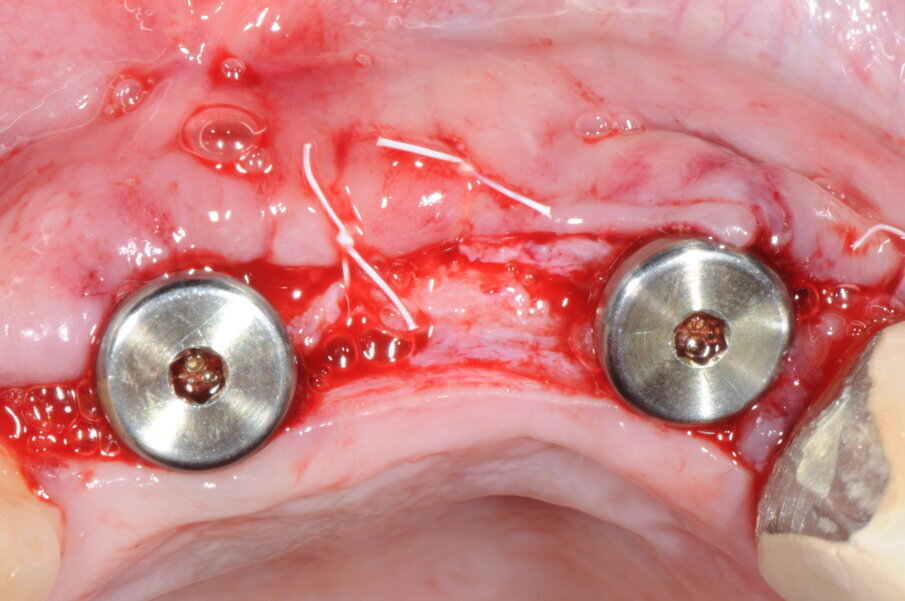

A 9 mesi è stata effettuata la seconda fase chirurgica in cui era prevista la rimozione delle viti di osteosintesi e il posizionamento degli impianti nei siti 1.1 e 1.2 (Blossomâ Intra-Lock System Europa). Grazie al volume osseo rigenerato risultava adeguato il posizionamento degli impianti come da progettazione protesica iniziale (Figg. 16-19).

Fig. 16 - Esposizione del sito rigenerato in visione occlusale.

Fig. 17 - Preparazione del sito implantare; impianti Blossom Intra-Lock.

Fig. 18 - Posizionamento delle viti tappo.

Fig. 19 - Sutura del lembo.